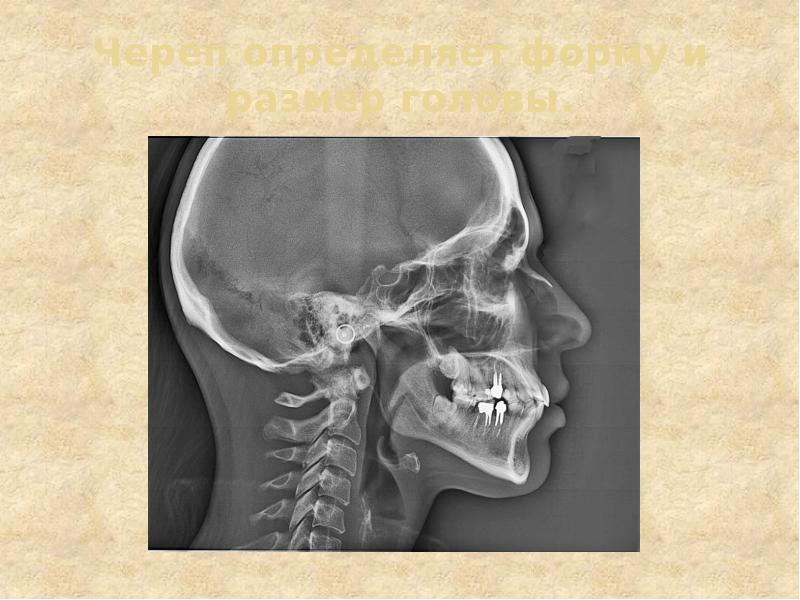

- 18. Строение черепа

- 19. Череп определяет форму и размер головы.

- 21. мозговой отдел лицевой отдел 8 костей: на поверхности затылочная 2